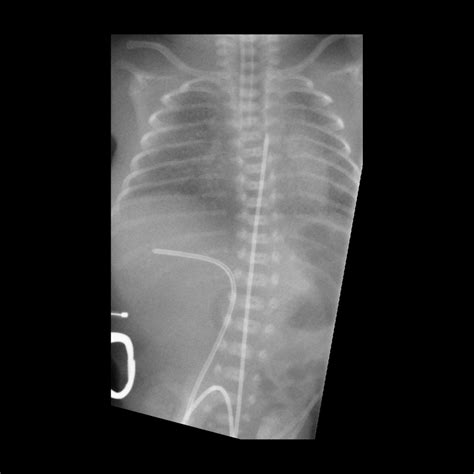

3. Insertion: The catheter is gently inserted into the umbilical vein, which is identified by its larger size and bluish color compared to the arteries. The catheter is advanced until it reaches the desired position, typically confirmed by ultrasound or X-ray.

5. Verification: The position of the catheter is verified using imaging techniques to ensure it is correctly placed in the inferior vena cava.